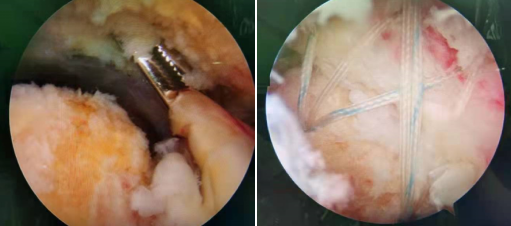

术中见撕裂的冈上肌腱(左图) 缝合后冈上肌覆盖良好(右图)

充分的术前准备后,由张传开主任、郝亮、王琳医生团队联合麻醉科、手术室等科室开始手术,取左肩峰下角入路进镜,分别建立前上、前下、外侧通道,插入关节镜,探查见肩关节周围软组织增生粘连,肩峰下骨质增生,肱二头肌长头腱水肿变性,镜下清理增生粘连组织,松解成形粘连软组织,打磨肩峰下增生的骨质,铆钉拧入肱骨结节间沟处,缝合后冈上肌覆盖良好,活动肩关节见肩袖附着点处稳定,固定可靠。手术十分顺利,术后,王大爷的肩关节疼痛立马得到缓解,术后第二天已经下地行走,进入康复锻炼中。